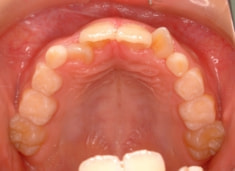

FX(フェイシャルアキシス)は85度なので東洋人の平均値に近く、下顎が前方に過剰成長するリスクは強くはありません。

しかしやはり上顎は劣成長で、下顎が優位な状態ではあります。

上下顎のギャップはありますが、顔面自体の幅径は良好な値を示していますので、スペース不足は拡大することによって解決できポテンシャルはあると考えられます。

左右の非対称もさほど強くありません。

骨年齢は実年齢よりも低めなので、今後下顎の旺盛な成長が見込まれます。

検査時のレントゲン分析では、上下顎の関係は、上顎の劣成長があり下顎前突傾向という値がでておりましたが、前歯ジャンプ後はフェイスマスクの効果もあり、上下顎の関係は正常化しています。

上顎が若干優位になっていますので、今後の下顎の成長のための貯金になっているくらいです。